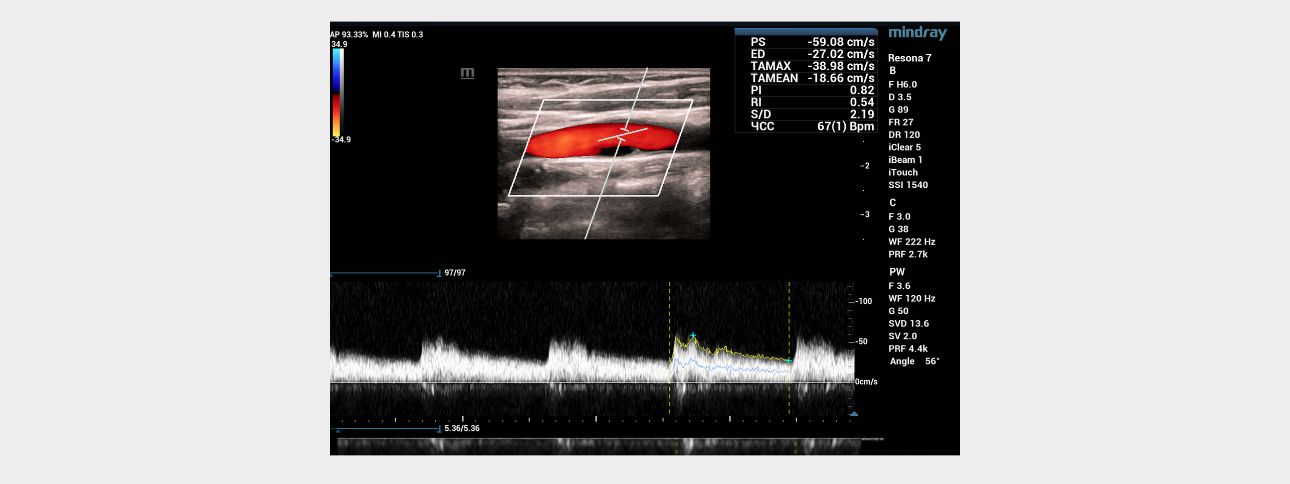

aotid-web-v-flow-fig3-pc

Fig 3. Ultrasound of the carotid sinus in spectral Doppler mode.

Blood flow with normal velocity parameters (Vs=59 cm/s) is recorded above the anechoic area.